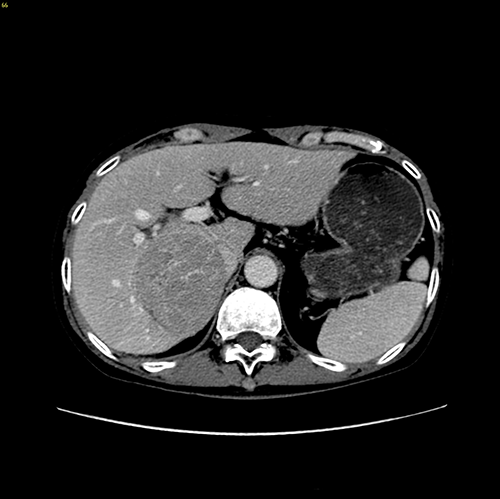

右肝肿瘤---右半肝切除